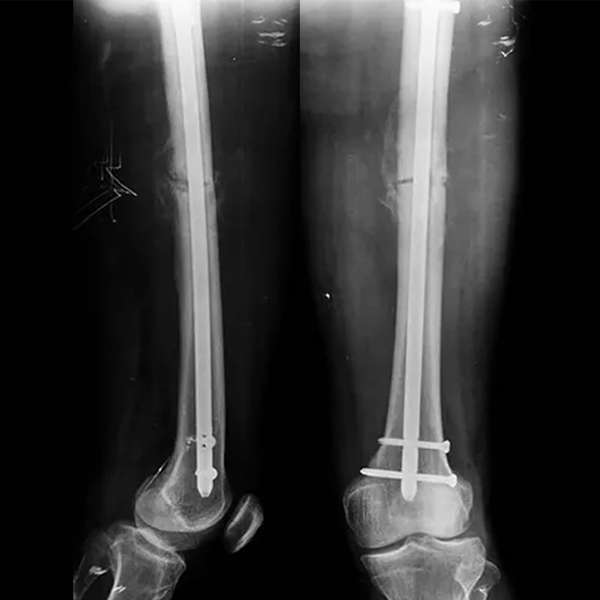

Le système d'ongles intramédullaire est un dispositif de fixation interne utilisé pour traiter les fractures osseuses longues (par exemple, fémur, tibia, humérus). Sa conception consiste à insérer un clou principal dans le canal médullaire et à le fixer avec des vis de verrouillage pour stabiliser la fracture. En raison de sa nature peu invasive, de sa stabilité élevée et de ses excellentes performances biomécaniques, il est devenu une option clé en chirurgie orthopédique moderne.

Le corps principal de l'ongle intramédullaire, généralement en titane ou en acier inoxydable, inséré dans le canal médullaire pour assurer la stabilité axiale.

Utilisé pour fixer l'ongle principal à l'os, empêchant la rotation et le raccourcissement. Comprend des vis de verrouillage statiques (fixation rigide) et des vis de verrouillage dynamiques (permettant une compression axiale).

Cas1

Cas2